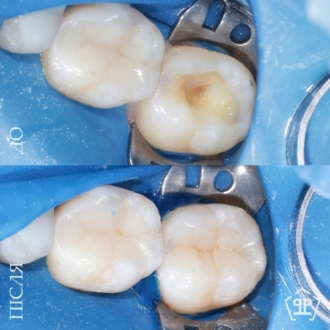

Результат лечения глубокого кариеса и художественная реставрация